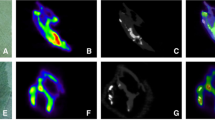

In contrast to the dense lesions identified on CT, localization of fluoride ions may identify proinflammatory lesions. In the absence of osteoclastic activity, some components of an inflammatory lesion, such as the persistence of apoptotic bodies (which occur in advanced atheroma due to lack of phagocytosis of apoptotic macrophages) serve as a nidus for calcification [44]. This amorphous crystalline structure has a surface composed of many different ions including monovalent, divalent, and trivalent species of both positive and negative charge. 18F-fluoride ions exchange with hydroxyl ions (OH-). Because of the small size of the individual crystals, an enormous surface area is exposed [45] (Fig. 2). A major problem with the use of FDG or 18F-fluoride PET/CT to identify vascular inflammation is the limited resolution of the scanner. The 3–5 mm in plane resolution often limits the ability to define the intense small regions of focal inflammation that may be present in symptomatic lesions. A study by Masteling and colleagues [46] describes this problem very well. These investigators incubated 17 fresh carotid endarterectomy specimens with FDG, imaged the specimens with microPET, and correlated the FDG uptake with the focal presence of macrophages (identified by CD68 immunostaining). The investigators observed a striking topographic correlation between the sites of uptake and the location of macrophages, which was not resolved in vivo on scans performed using standard commercial PET/CT scanners, but was seen on the microPET images of endarterectomy specimens. It is likely that 3 mm spatial resolution would also limit the ability to identify microcalcifications with 18F-fluoride imaging. The histopathology of atheroma suggests that small lesions with high focal FDG or 18F-fluoride uptake are the most vulnerable. When these lesions are imaged reliably, vascular PET imaging will be ready for routine clinical use.